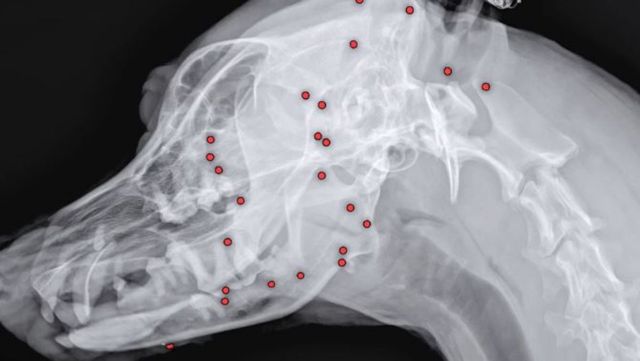

온몸에 총알이 박힌 백구의 X-ray 이미지. / VIP 동물의료센터 인스타그램

VIP 동물의료센터 성북점은 구조 후 해외 입양을 준비 중이던 유기견 백구의 X-ray 찍었는데 70개 넘는 산탄총 파편이 몸 곳곳에 박혀 있었다고 25일 전했다.

안승엽 원장은 "총알이 머리 쪽부터 어깨, 가슴통, 엉덩이, 다리까지 너무 많이 있었다"며 "살아있는 게 기적"이라고 말하면서 탄알 성분이 귀동이의 몸에 안 좋은 영향을 끼칠 수 있기 때문에 제거 가능한 부분에 대해 수술하기로 했다.

안 원장은 우선 백구의 얼굴을 중심으로 최대한 많은 파편을 제거하기로 했다고 밝혔다. 70여 개 이상의 탄알을 한 번에 모두 제거하는 것은 현실적으로 불가능했기 때문이다. 이날 수술을 통해 총 26개의 파편이 몸 밖으로 제거됐다.

제거된 파편들은 향후 성분 분석을 통해 추가 수술도 검토될 전망이다. 여전히 백구의 몸에는 약44개의 파편이 남아있는 상태다.